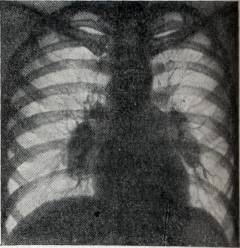

Лимфосаркома средостения (грудной клетки)

- общее недомогание

- одышка

- приступообразный сухой кашель

- бледный цвет лица

- синюшность губ

- высокая температура

- хрипов при прослушивании обычно нет

- Рентгенография:

- затемнение в лимфатических узлах

- поражение нескольких лимфоузлов